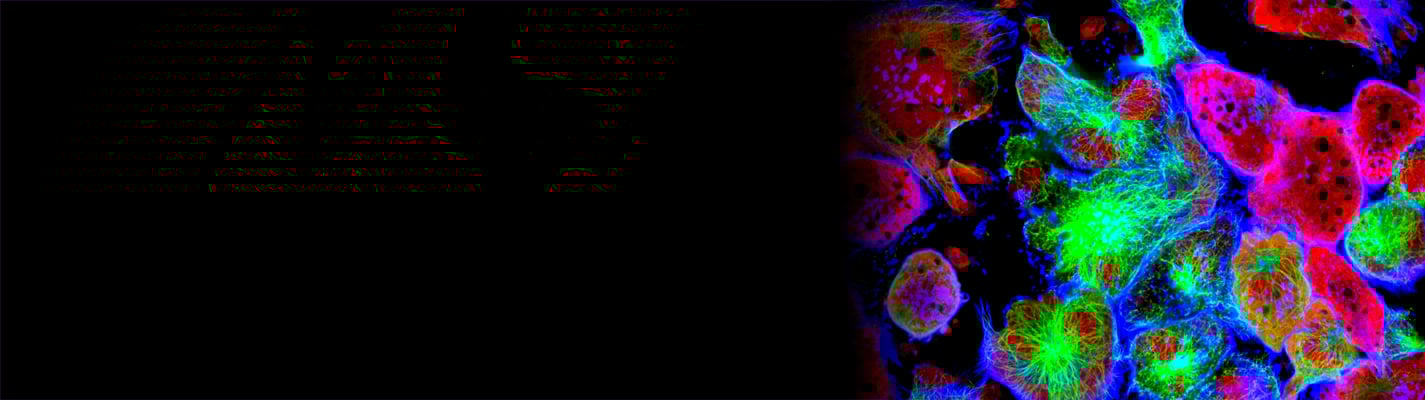

The importance of imaging in drug discovery

As the demand for personalised medicine and targeted therapies grows, the need for customised imaging solutions in drug discovery becomes more pronounced.